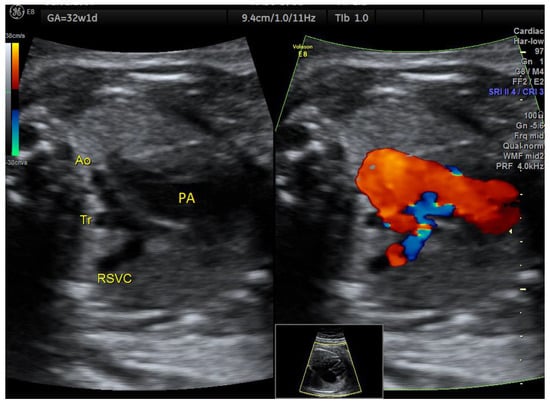

| IAoA | 1 | perimembranous VSD | - | 3VT | + | 0 | 1 | 0 | 1/1 |